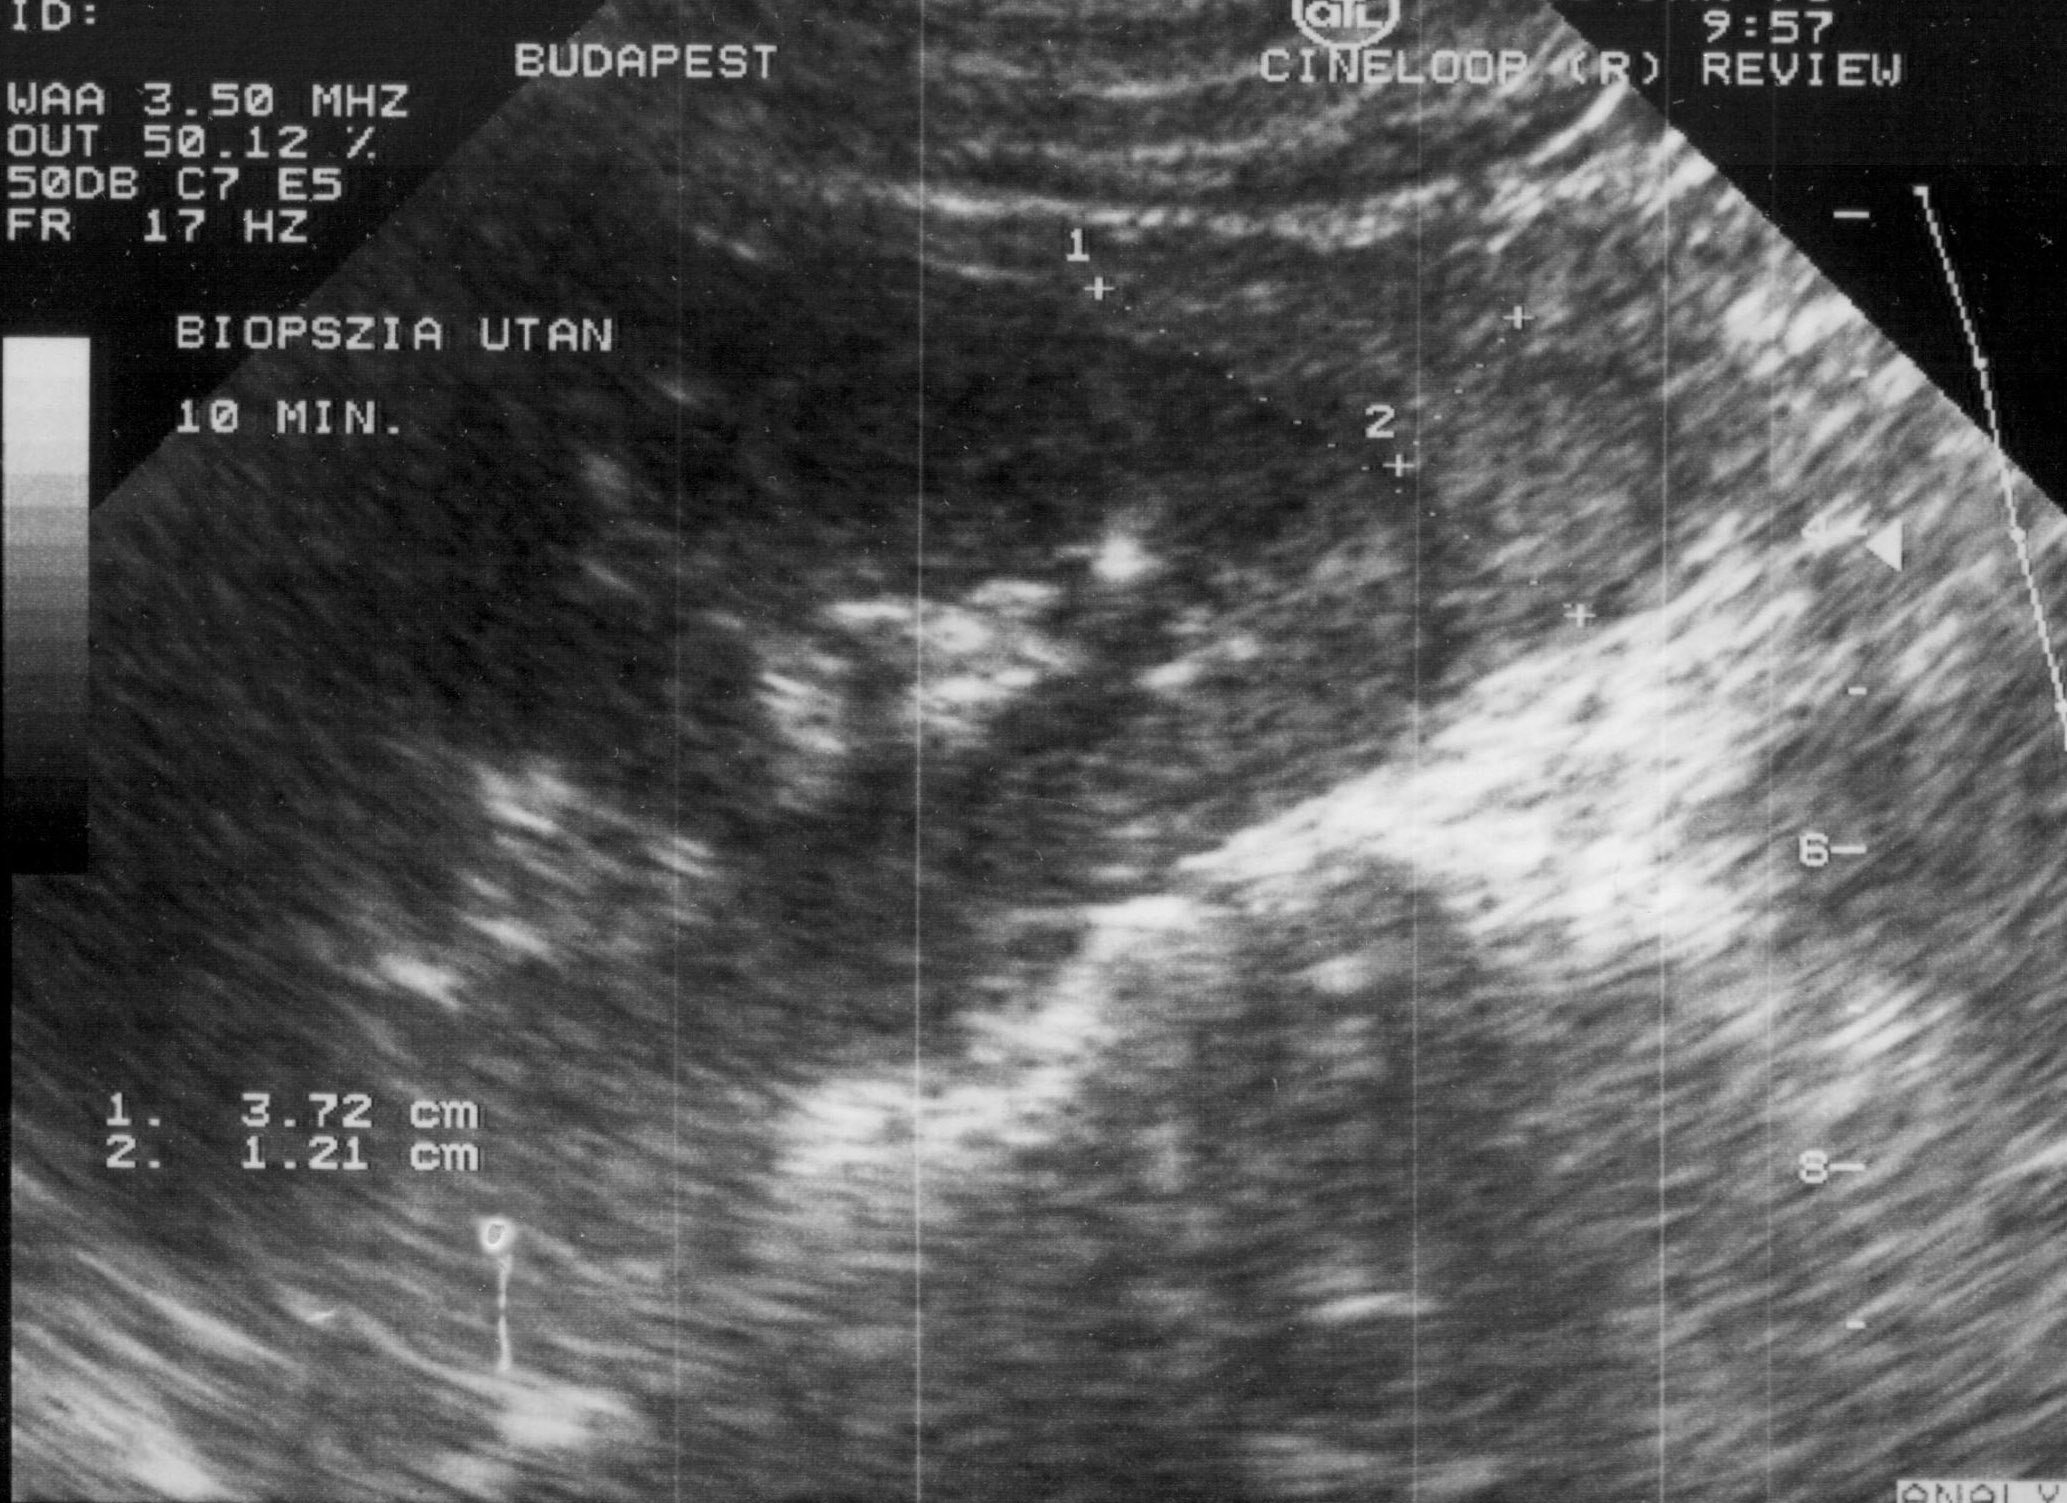

- Hemorrhage (subcapsular (figure 12.), parenchymal, intraabdominal (figure 13.), intrathoracic, pseudoaneurysm),

Image

Figure 12. – US guided renal biopsy, subcapsular hemorrhage (5 minute control)

Figure 13. – US guided renal biopsy, serious retroperitoneal and intraabdominal hemorrhage, with active bleeding (20 hour control)